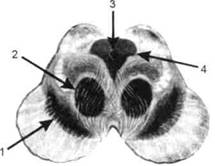

Спинной мозг является цилиндрическим образованием с толстыми стенками, которое на поперечном разрезе представлено двумя типами нервной ткани — серым веществом тел нейронов, сконцентрированных в центральной части в виде буквы «Н» или «бабочки», и белым веществом, образованным пучками восходящих и нисходящих аксонов и дендритами. «Крылья бабочки» разделены на два передних и два задних рога. Передние рога содержат тела моторных нейронов, эфферентные аксоны которых направляются в составе спинномозговых нервов к мышцам. Задние рога содержат клетки промежуточных нейронов, к которым подводятся афферентные волокна, доставляю-. щие чувствительные импульсы с периферии. Топография белого вещества на поперечных срезах спинного мозга такова, что позволяет говорить о передних, задних и боковых столбах, расположенных в соответствующих промежутках между передними и задними рогами (рис. 5). В срединных отделах серого вещества проходит центральный канал, содержащий спинномозговую жидкость. Анализ организации нейронных цепей в задних рогах спинного мозга позволил сделать вывод, что эта часть центральной нервной системы не является только передаточным механизмом, в котором афферентные сигналы транслируются по восходящим путям. Здесь отдельные сенсорные модальности подвергаются сложной переработке, в его многочисленных нейронных цепях и синаптических контактах происходят интегративные процессы, приводящие к тому, что значительное число импульсов, входящих в спинной мозг, отфильтровывается и не достигает больших полушарий.

Рис. 5. Горизонтальный разрез верхнего отдела спинного мозга: / — нежный и клиновидный канатики, образующие задний столб; 2 — задний рог; 3 — боковой столб; 4 — передний рог; 5— передний столб; 6 — центральный канал